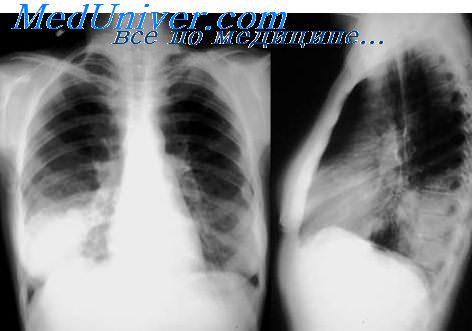

image

Коваленко В.Л. и др. при клинико-патологоанатомическом сопоставлении 120 случаев пневмомикозов установил, что во всех возрастных группах грибковые поражения легких развиваются в связи с наличием у пациента первичного или вторичного иммунного дефицита. В качестве основного или фонового заболевания могут выступать хронический бронхит с бронхоэктазами, хронические абсцессы. При этом характер тканевых реакций в легких при пневмомикозах наряду с тинкториальными свойствами возбудителя и особенностями фоновой патологии определяется напряженностью местного клеточного иммунитета. О снижении местных клеточных и субклеточных факторов защиты при хронической кандидоинфекции свидетельствуют исследования, проведенные Сардыко Н.В. и др. Особенности защитных клеточных реакций при различных оппортунистических микозах в значительной степени зависят от взаимодействия макро-микроорганизма. В условиях иммунодефицита отмечается увеличение колонизации и инвазия возбудителя, изменение характера и выраженности тканевых и клеточных реакций.

Существует мнение, что воспаление легких является пусковым механизмом к развитию генерализованных инфекций бактериальной или грибковой природы.

Основным возбудителем аспергиллеза у человека является Aspergillus fumigatus. Aspergillus вызывает аспергиллему легких (сапрофитическая колонизация) и аллергический бронхолегочный аспергиллез (АВРА). В связи с этим будут различными и клинические проявления заболевания.